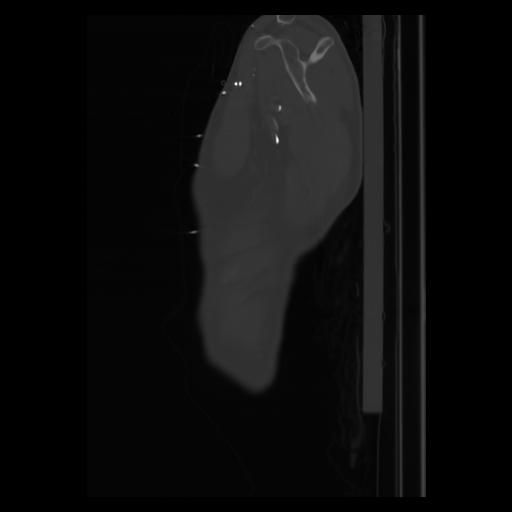

30 CUERPO,CE,Sagittal,3.000,CUERPO,Sagittal,